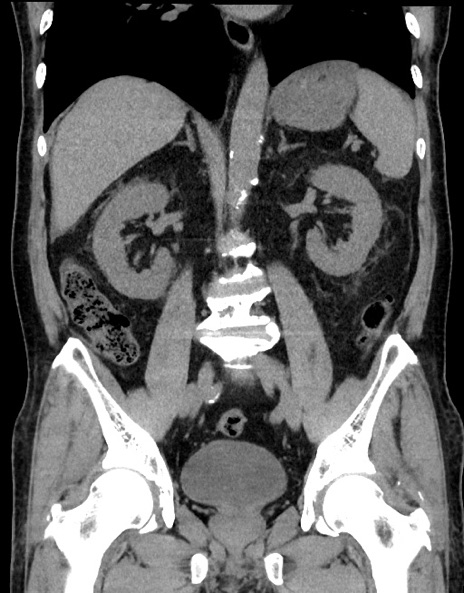

症例15(冠状断像)

【症例】70歳代男性

【主訴】腹痛

【現病歴】今朝から腹痛あり。全体的に痛い。特に左上の方。排ガスが今日はない。冷や汗が出る。

【既往歴】直腸癌術後

【身体所見】左側腹部〜上腹部に圧痛あり。腹膜刺激症状明らかなではない。軽度反跳痛。左下腹部に術後瘢痕あり。

【データ】WBC 7700、CRP 0.02

横断像